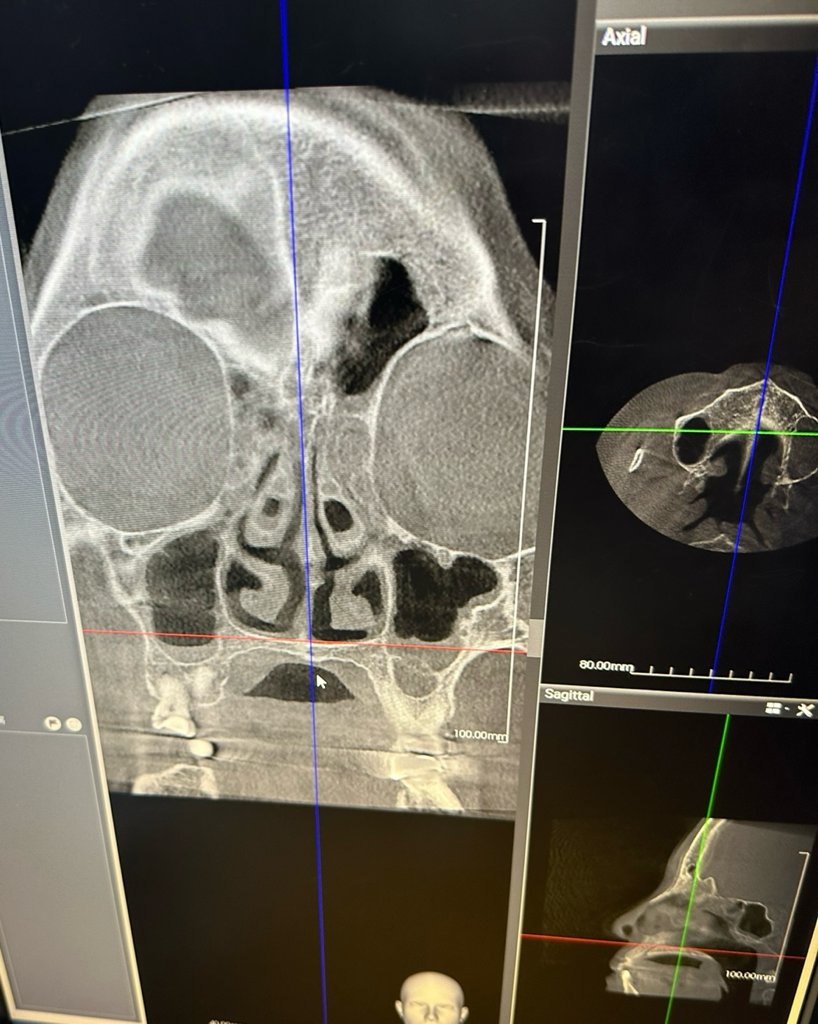

씨티를 찍었는데 축농증이 많이 심한 편인지 궁금합니다

씨티 찍었는데 축농증이 많이 심한 상태인지 궁금합니다

단편적 영상만으로는 평가가 어렵습니다만 부비동 내 분비물이 고여 있는 소견으로 정도가 심해 보이진 않습니다.

아래 사진 보시면 눈 밑에 부비동 (paranasal sinus)에 염증이 차있고 점막이 두꺼워져있는걸 볼 수 있습니다.

정상적으로는 검정색 공기만 들어있어야합니다.

작성자분의 부비동에는 농이 가득차있지는 않지만 오른쪽 (사진상 왼쪽)에는 소량의 염증이 보이고 왼쪽 부비동에는 조금 더 많은 염증이 관찰됩니다.

항생제를 복용해도 부비동은 혈액순환이 많이 떨어지는 구조라 치료가 얼마나 걸릴지 예상할 수는 없습니다.